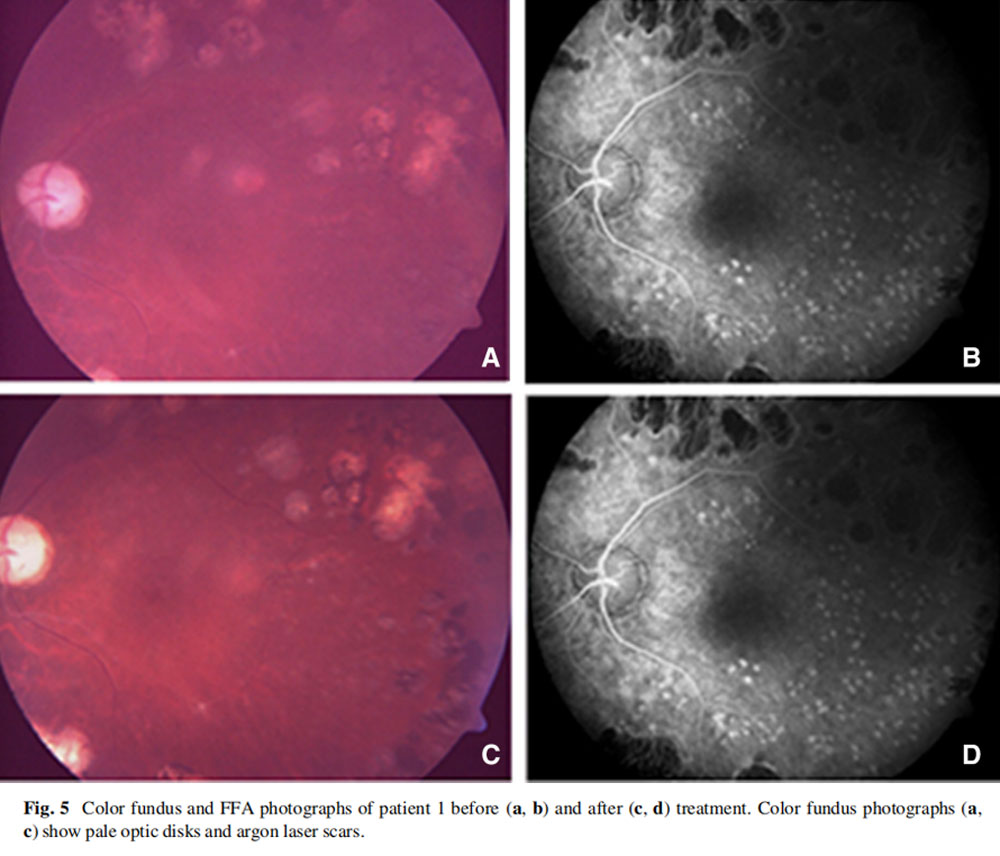

患者1:一名52歲男性,因糖尿病視網膜病變接受了雙側全視網膜氬激光光凝術,在過去2年中一直患有進行性視力喪失,AD-MSCs治療前右眼視力10/200,左眼視力2英尺(約0.6米)處的手部運動(HM),雙眼視神經蒼白,視野檢查顯示雙眼中央島狀結構,左眼較小,mfERG顯示雙眼振幅降低,OCT和RNFL均顯示雙眼黃斑、脈絡膜和神經纖維層變薄。

4名患者在AD-MSC治療后,未出現并發癥,眼底熒光血管造影(FFA)檢查均未發現病變(圖5),未經治療的右眼在所有檢查中均出現惡化跡象。